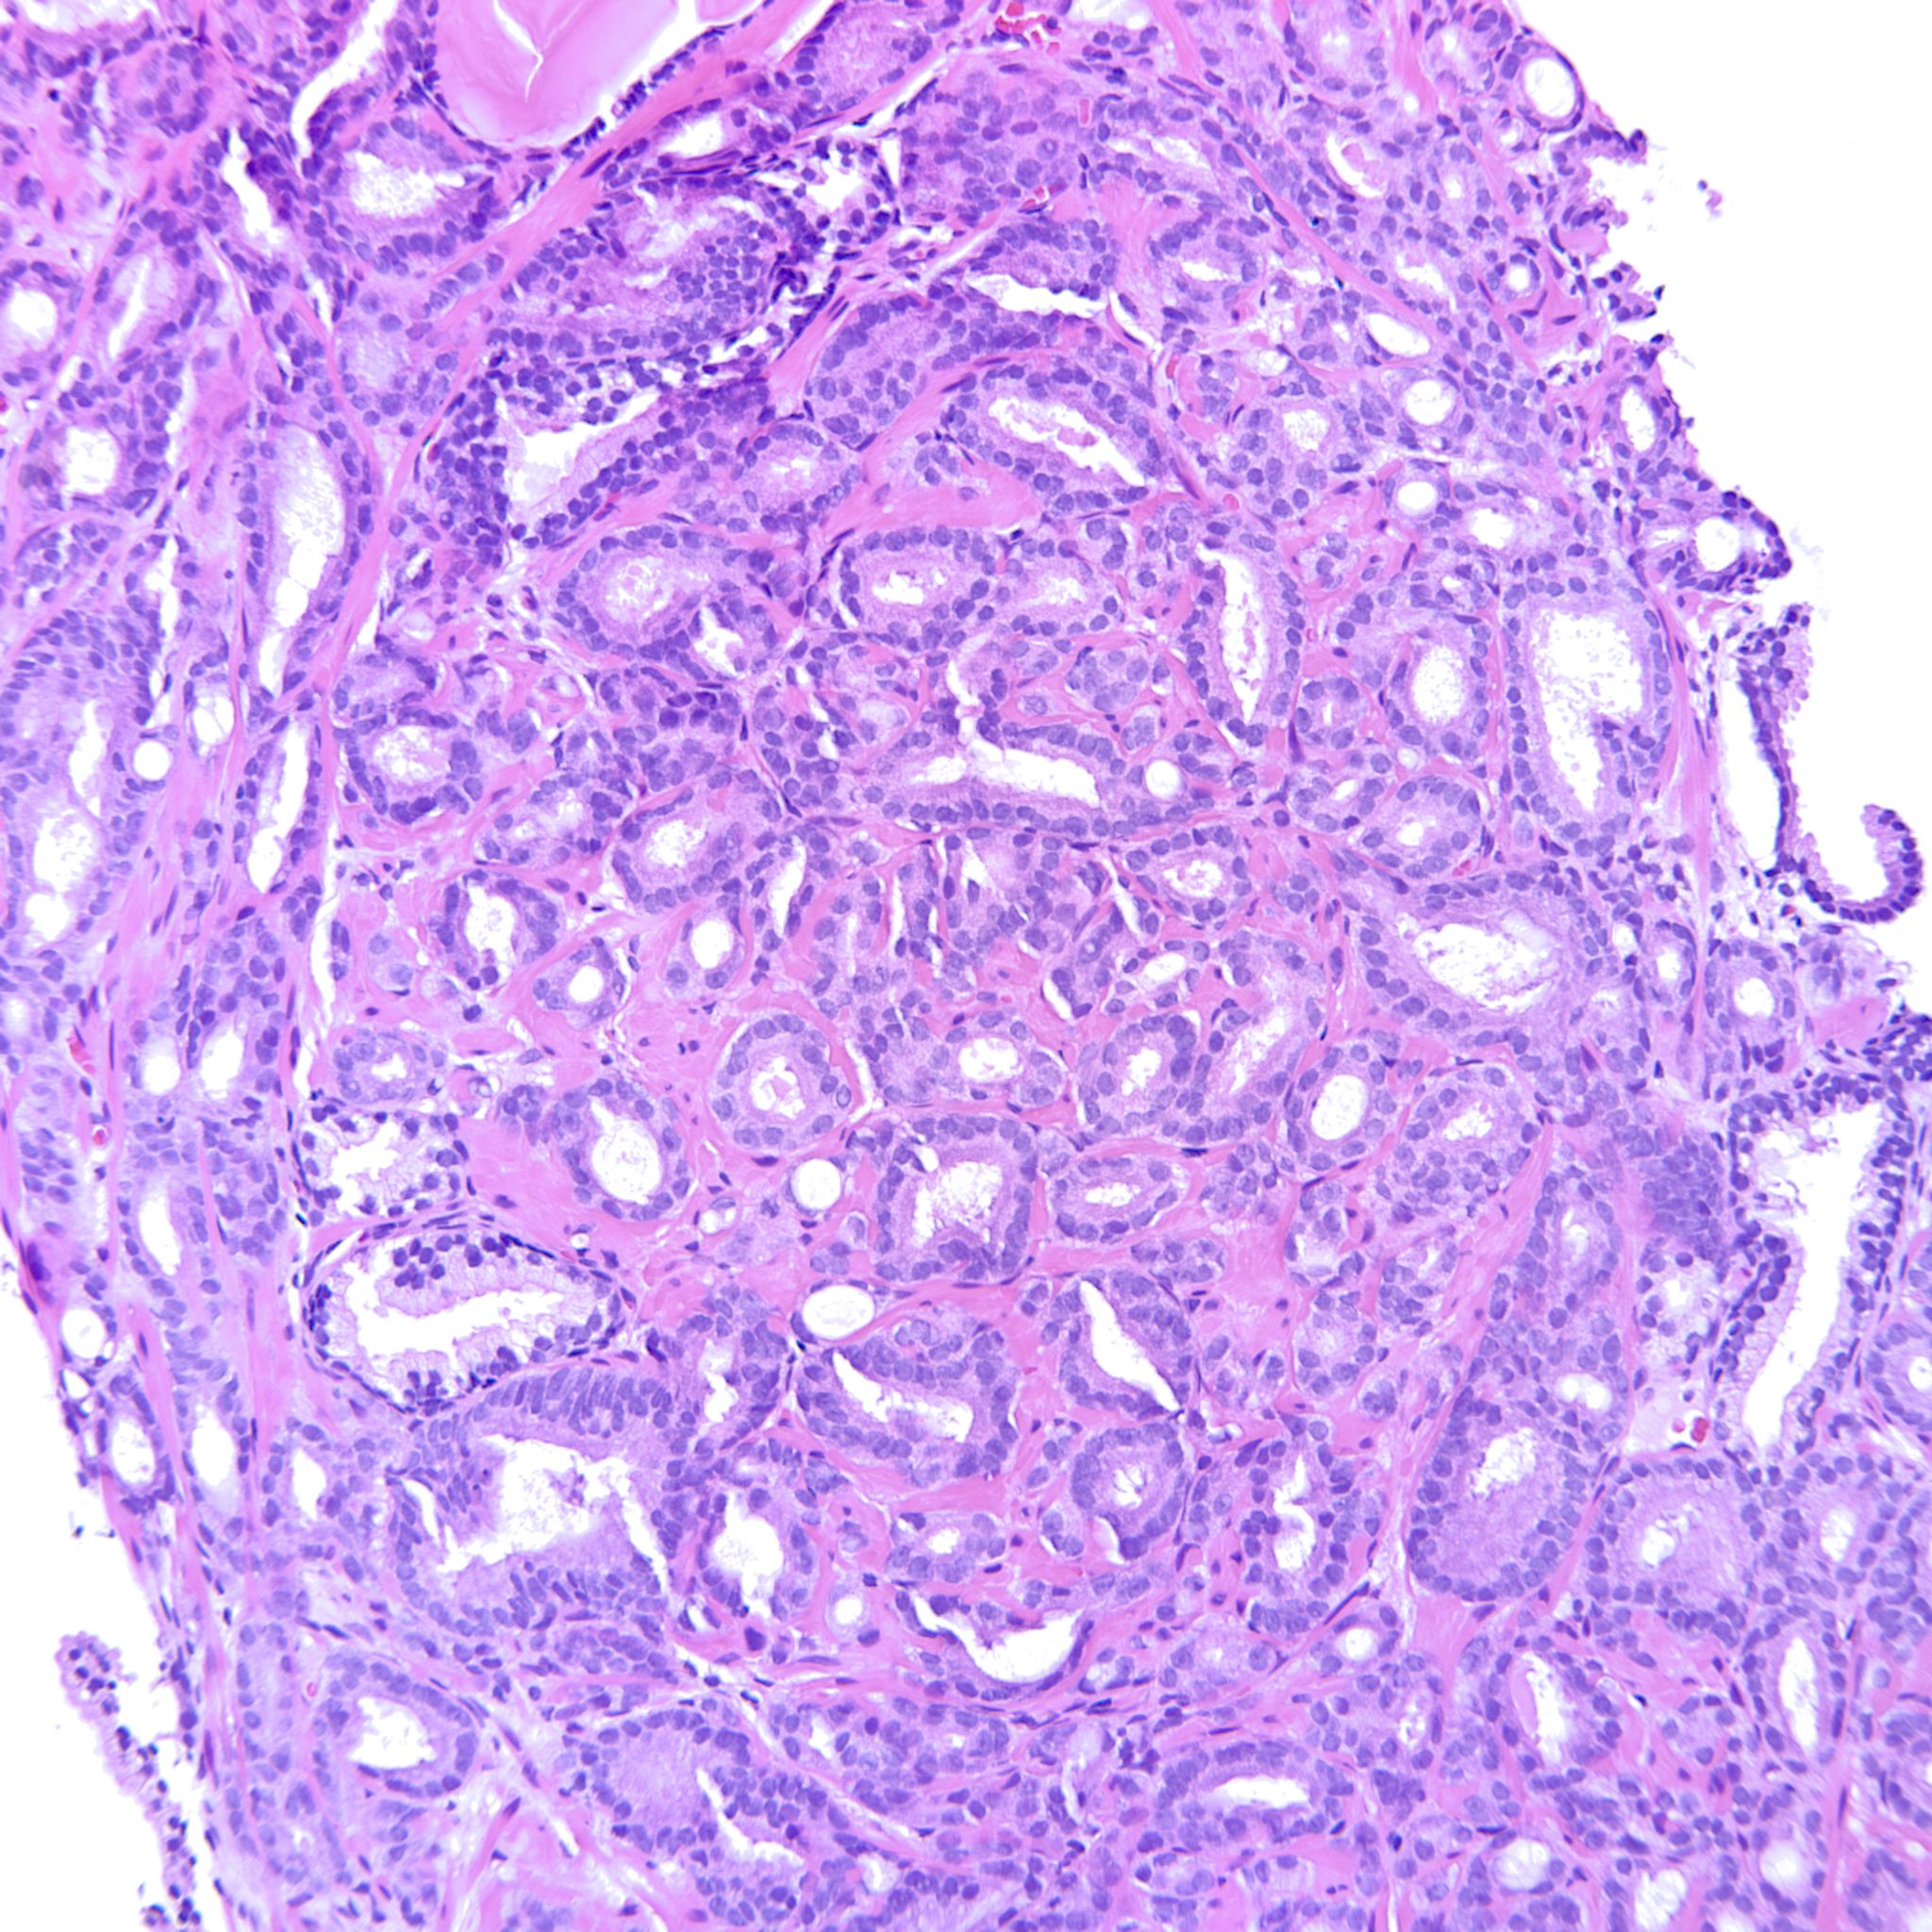

Prostate cancer grading

Case ID: 214